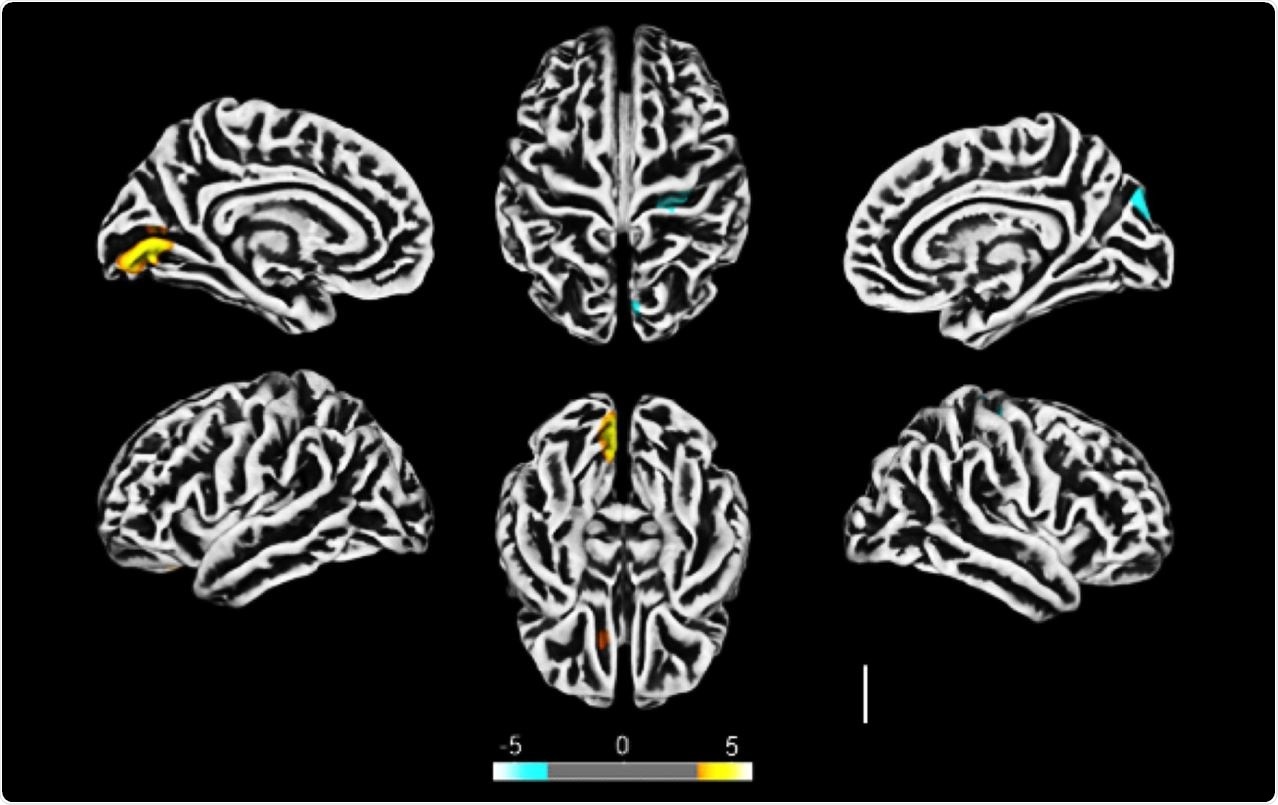

Altered cerebral cortical thickness is associated with neuropsychiatric symptoms in COVID-19 patients. a) Surface-based morphometry using high-resolution 3T MRI. Yellow represents areas of decreased cortical thickness: left lingual gyrus, calcarine sulcus (and cuneus), and olfactory sulcus (and rectus gyrus) . Blue represents areas of increased cortical thickness: central sulcus (precentral and postcentral gyrus) and superior occipital gyrus. Representative image of the analysis of 81 subjects tested positive for SARS-CoV-2 who had mild respiratory symptoms and did not require hospitalization or oxygen support compared to 145 healthy volunteers (without diagnosis of COVID-19) . The analysis was performed within a median interval of 54 days. b) Correlation between BAI performance and right orbital gyrus thickness. The data depicts Pearson’s correlation coefficient . c) Correlation between TRAIL B performance and right gyrus rectus thickness. Data depict Pearson’s correlation coefficient and region of interest in representative images.

All the recruited patients underwent MRI scanning of the brain. The team saw reduced cortical thickness in some areas of the brain and increased thickness in other parts.